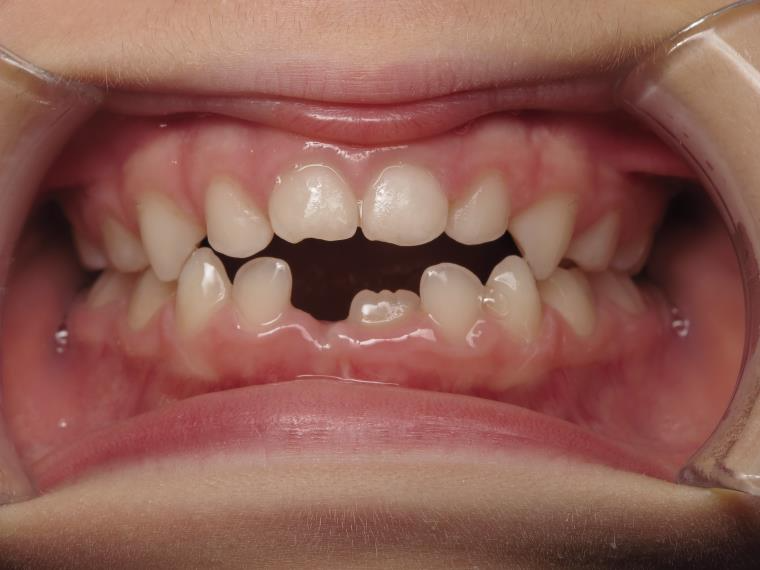

14 béance inversé gauche 5 ans

inversion postérieur coté droit et espace entre l'arcade du haut et du bas (béance)